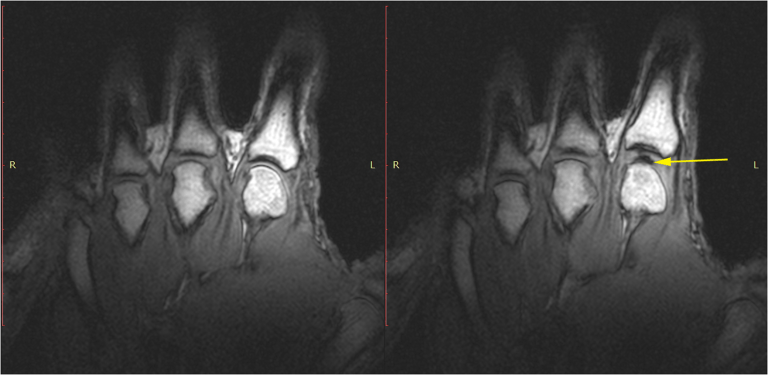

IRM d’une articulation avant et après le phénomène de Vacuum. Sur l’image de droite on observer la formation d’une cavité au bout de la flèche jaune. Source: Plos One, Real-Time Visualisation of Joint Cavitation. Pour voir la vidéo sur Youtube: https://www.youtube.com/watch?v=_ZNENkkf5Uw |

L’ajustement chiropratique entraîne un étirement très rapide de la capsule articulaire au-delà de la limite physiologique normale, ce qui augmente le volume de la capsule et crée un « vacuum » ou une pression négative à l’intérieur de l’articulation. Le terme précis pour nommer ce phénomène est la cavitation, mais pour faire une image, on peut l’appeler la « bulle ». L’oxygène, le dioxyde de carbone et l’azote dissous dans le liquide synovial passent de la forme liquide à la forme gazeuse, remplissant ainsi le vide. On pourrait comparer cela à l’ouverture d’une bouteille de champagne. Au moment où la bouteille s’ouvre, les gaz dissous dans le liquide s’échappent. On aperçoit alors les bulles remonter à la surface.

Si les scientifiques s’entendent sur la formation de la « bulle », il existe toutefois deux théories expliquant l’origine du son, qui se font bataille depuis plusieurs décennies. La première veut que ce soit l’éclatement de la bulle (ou de microbulles de gaz) qui entraîne le « crac » sonore alors que l’autre soutient que c’est plutôt la formation de la bulle qui produirait le bruit typique. Deux études plus récentes (2015 et 2018), une démontrant la cavitation sous résonance magnétique et l’autre présentant plutôt un modèle mathématique, ont gardé les deux théories sur le tapis.

IRM d’une articulation avant et après le phénomène de Vacuum. Sur l’image de droite on observer la formation d’une cavité au bout de la flèche jaune. Source: Plos One, Real-Time Visualisation of Joint Cavitation. Pour voir la vidéo sur Youtube: